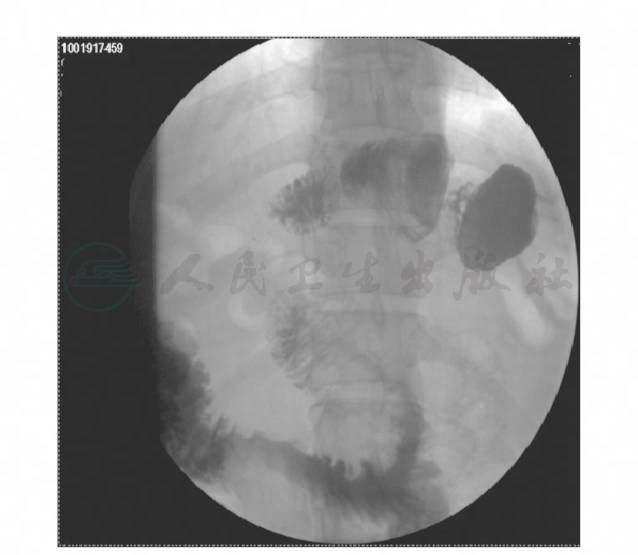

术后出院前行泛影葡胺造影,显示胃小囊形态、容量正常,吻合口通过良好。造影剂无明显渗漏(图3)。

图3 消化道造影显示胃小囊形态、容量正常,吻合口通过良好